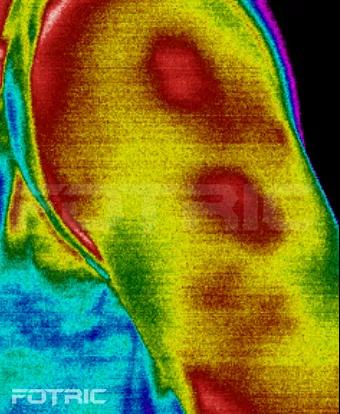

紅外熱像儀不僅可以應用公共場所的測溫篩查,還可以應用于醫(yī)學方面的研究,同時還可以通過對異常機體的照射產(chǎn)生熱像圖,為醫(yī)生對病人病情的診斷做出推論。因此,紅外熱像儀對我們來說是百利而無害的。

陣發(fā)性左前胸疼痛檢測

肌肉慢性僵化檢測